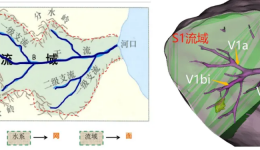

胰腺、肝脏、脾脏及腹膜后区域的复杂腹腔镜肿瘤切除手术,因其操作复杂、风险高、根治率低,且病灶在体内隐藏至深、常与侵犯邻近脏器关系复杂,被喻为外科领域的“天花板”技术。而在茂名市人民医院,该项技术已能成熟开展——近日,在茂名市人民医...

为进一步推动区域医疗技术协同发展,提升肝胆外科微创手术水平,3月1日至2日,广东省医学科学院副院长、广东省人民医院(以下简称“省医”)外科主任陈汝福,省医肝胆外科主任金浩生教授率团队到茂名市人民医院(以下简称“茂医”)开展学术交流和...